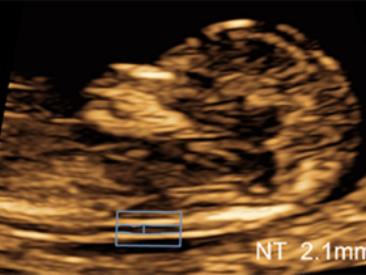

ImĂĄgenes clĂnicas